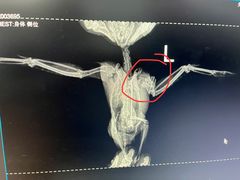

• 瑞派·关忠动物医院·异宠专科·犬猫肿瘤·皮肤专科(望京店)

• -瑞派·关忠动物医院·异宠专科·犬猫肿瘤·皮肤专科(望京店)